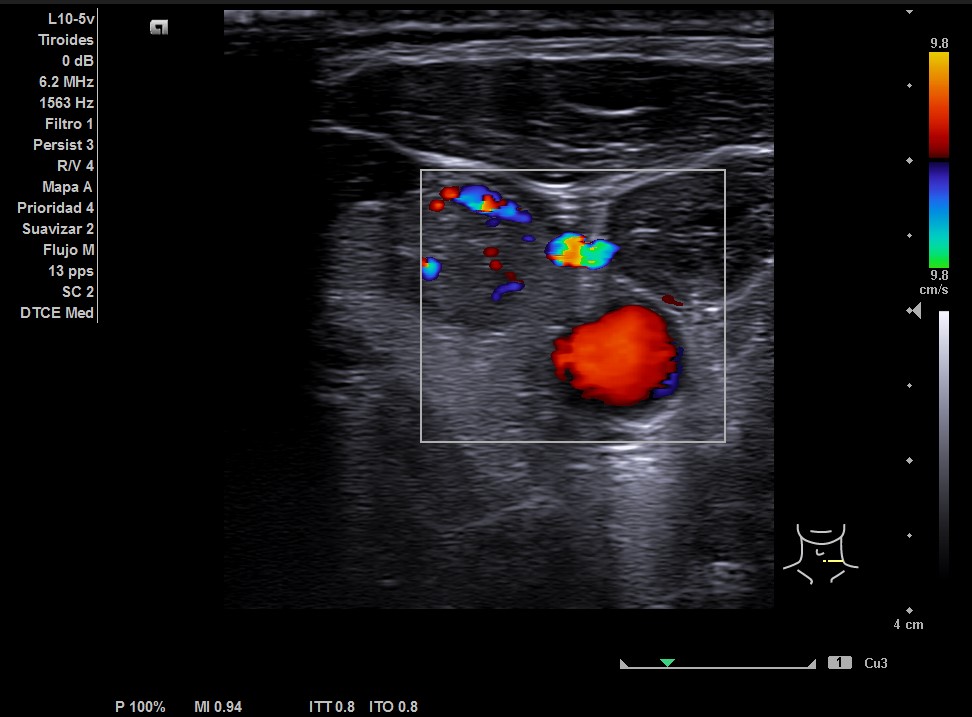

En la ecografía tiroidea se observa en LTI nódulo de 10 mm de bordes mal definidos, lobulado, mayormente sólido, más alto que ancho, isoecogénico, halo periférico hipoecoico, vascularización difusa, que sugiere TIRADS 5. Ausencia de flujo en Vena yugular interna izquierda, ensanchada, que sugiere trombosis yugular aguda o subaguda y junto a ella, posible conglomerado adenopático.